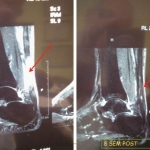

Vision en RMN: Rotura antigua del Tendon de Aquiles; antes y después de tratamiento con PRP